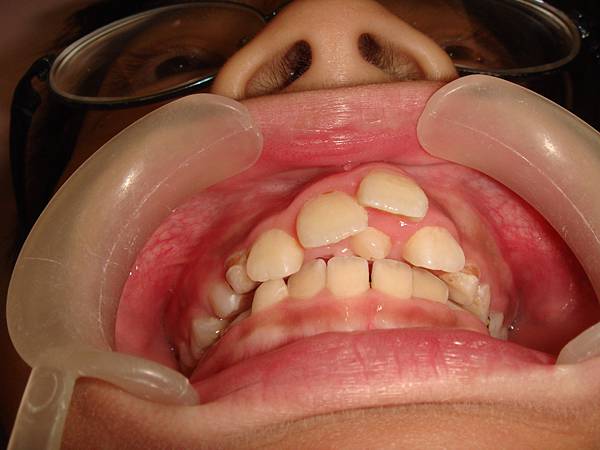

(上圖為本診所案例)

多生牙究竟是什麼?該怎麼處理?有許多民眾遇到相同問題時,都會有很多疑問產生;王太太就碰到類似情形,她看到讀小四的兒子牙齒排列不整齊,便帶他到牙醫診所請牙醫師檢查。牙醫師為病患檢查口腔狀況後,又照了一些

X光片。牙醫師拿著

X光片向王太太說明:「小明因為牙顎弓較小,造成齒列排列不整,另外在上顎正中門齒中間長了一顆多生牙。」王太太心想:什麼是多生牙?多一顆牙齒是好還是壞?